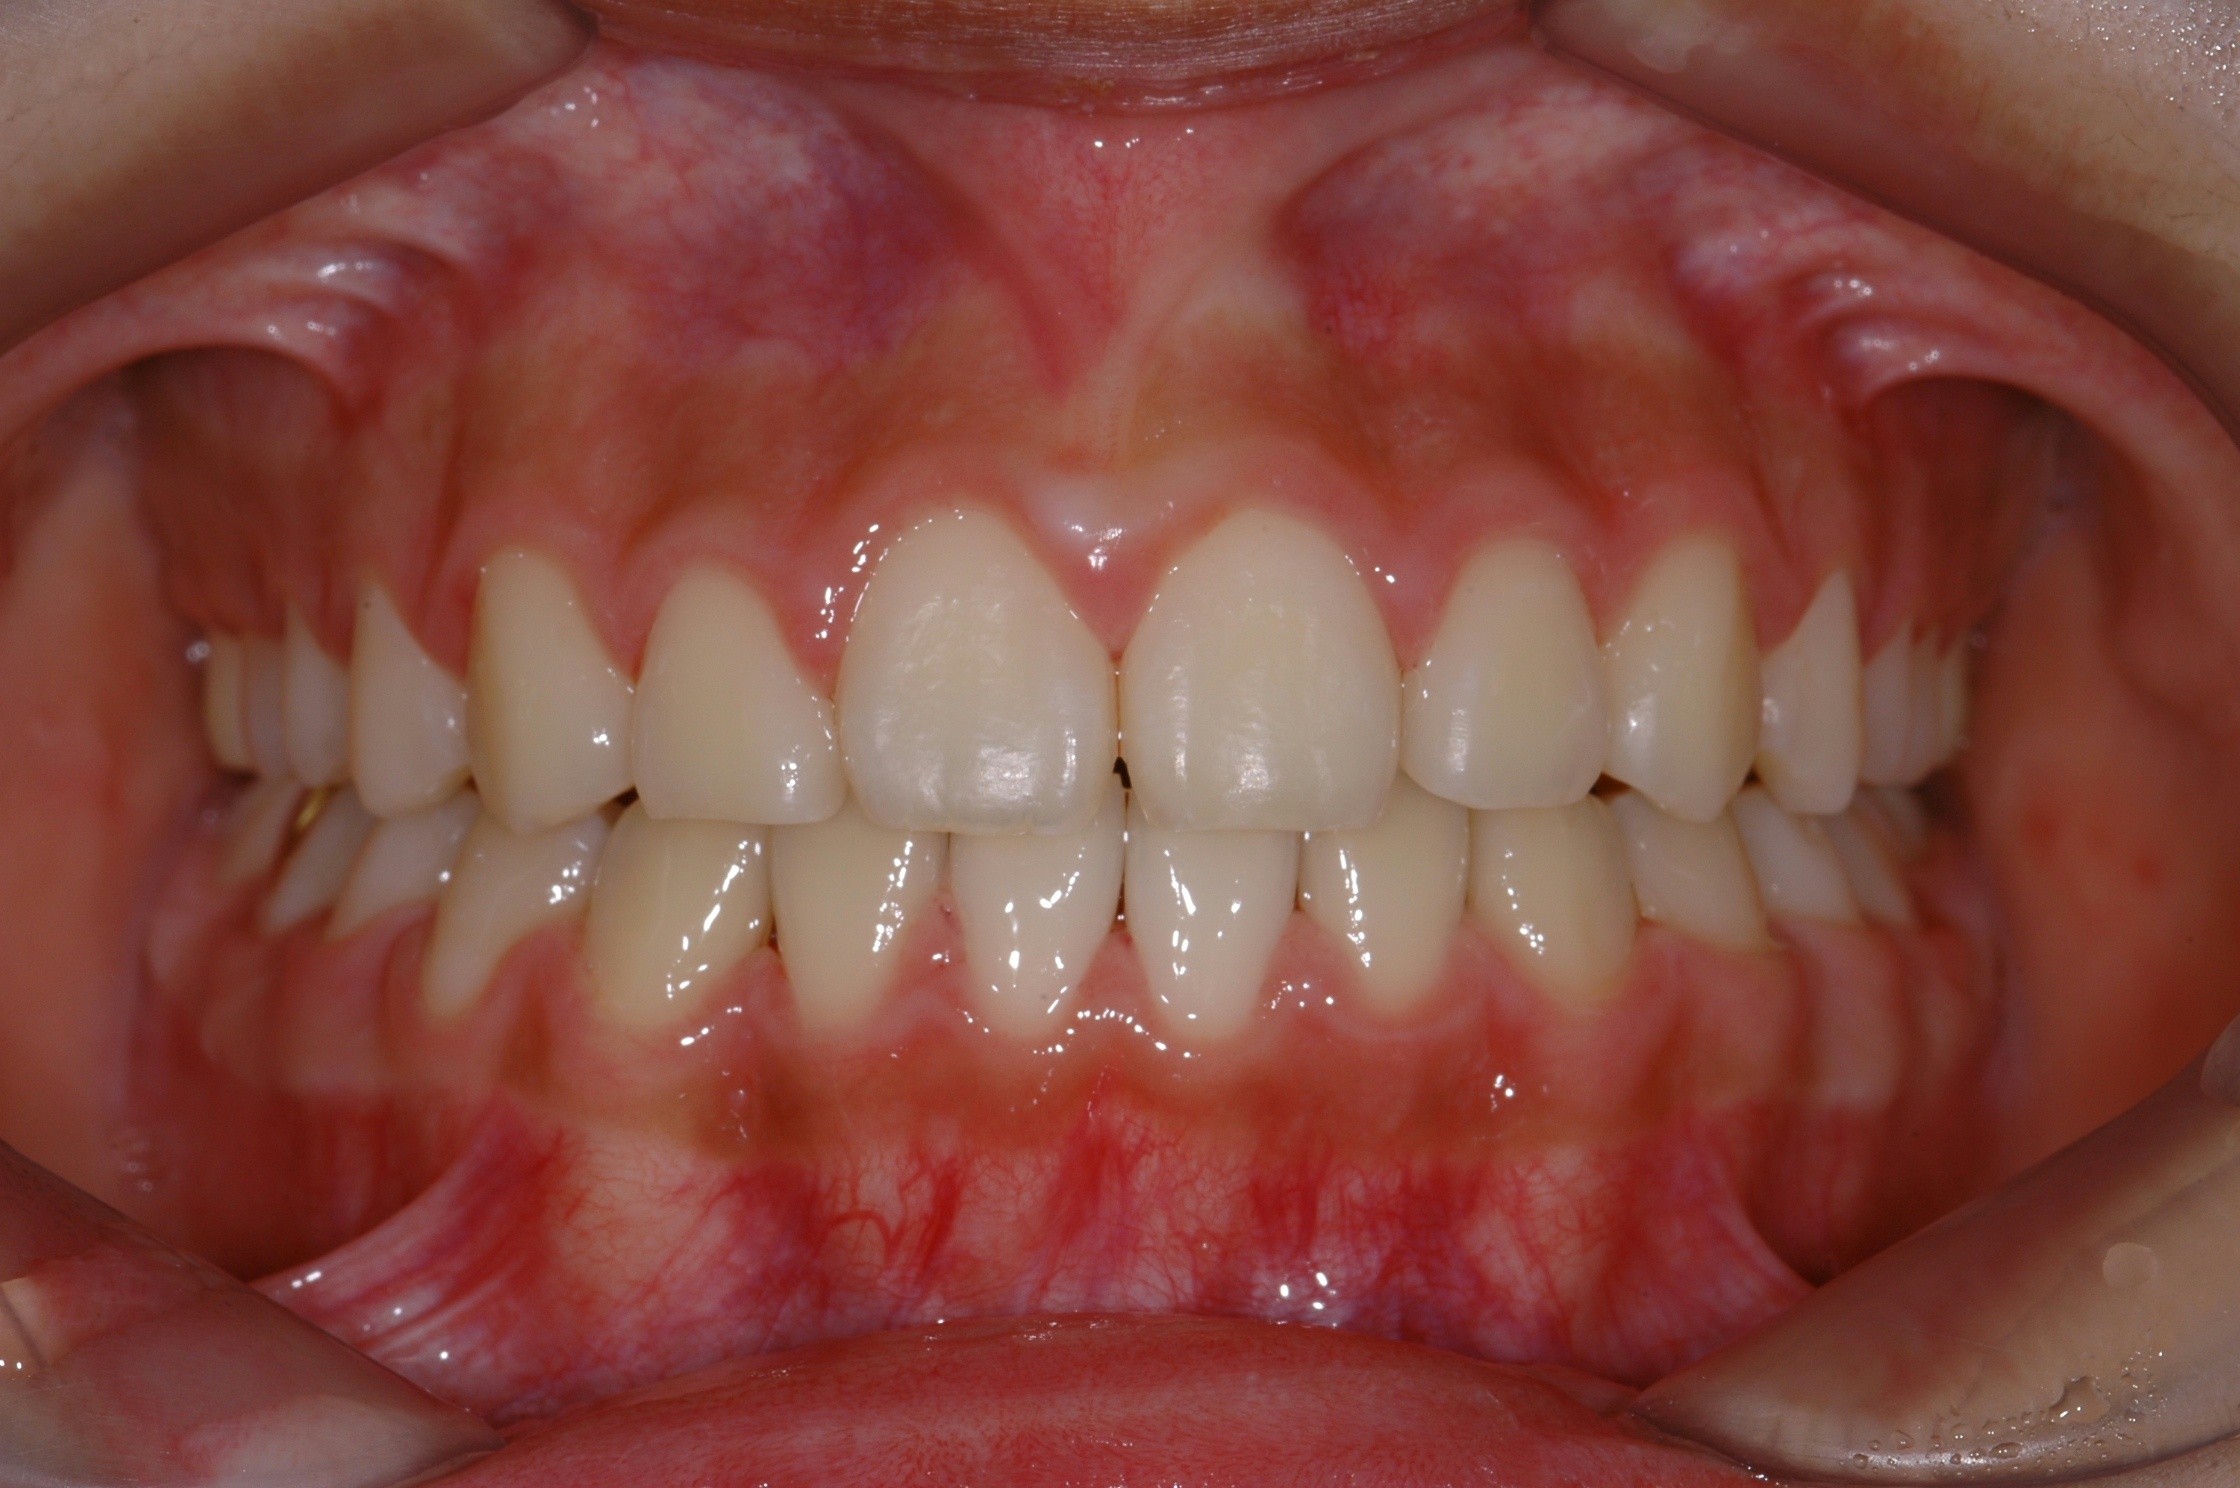

치료 후 사진입니다.